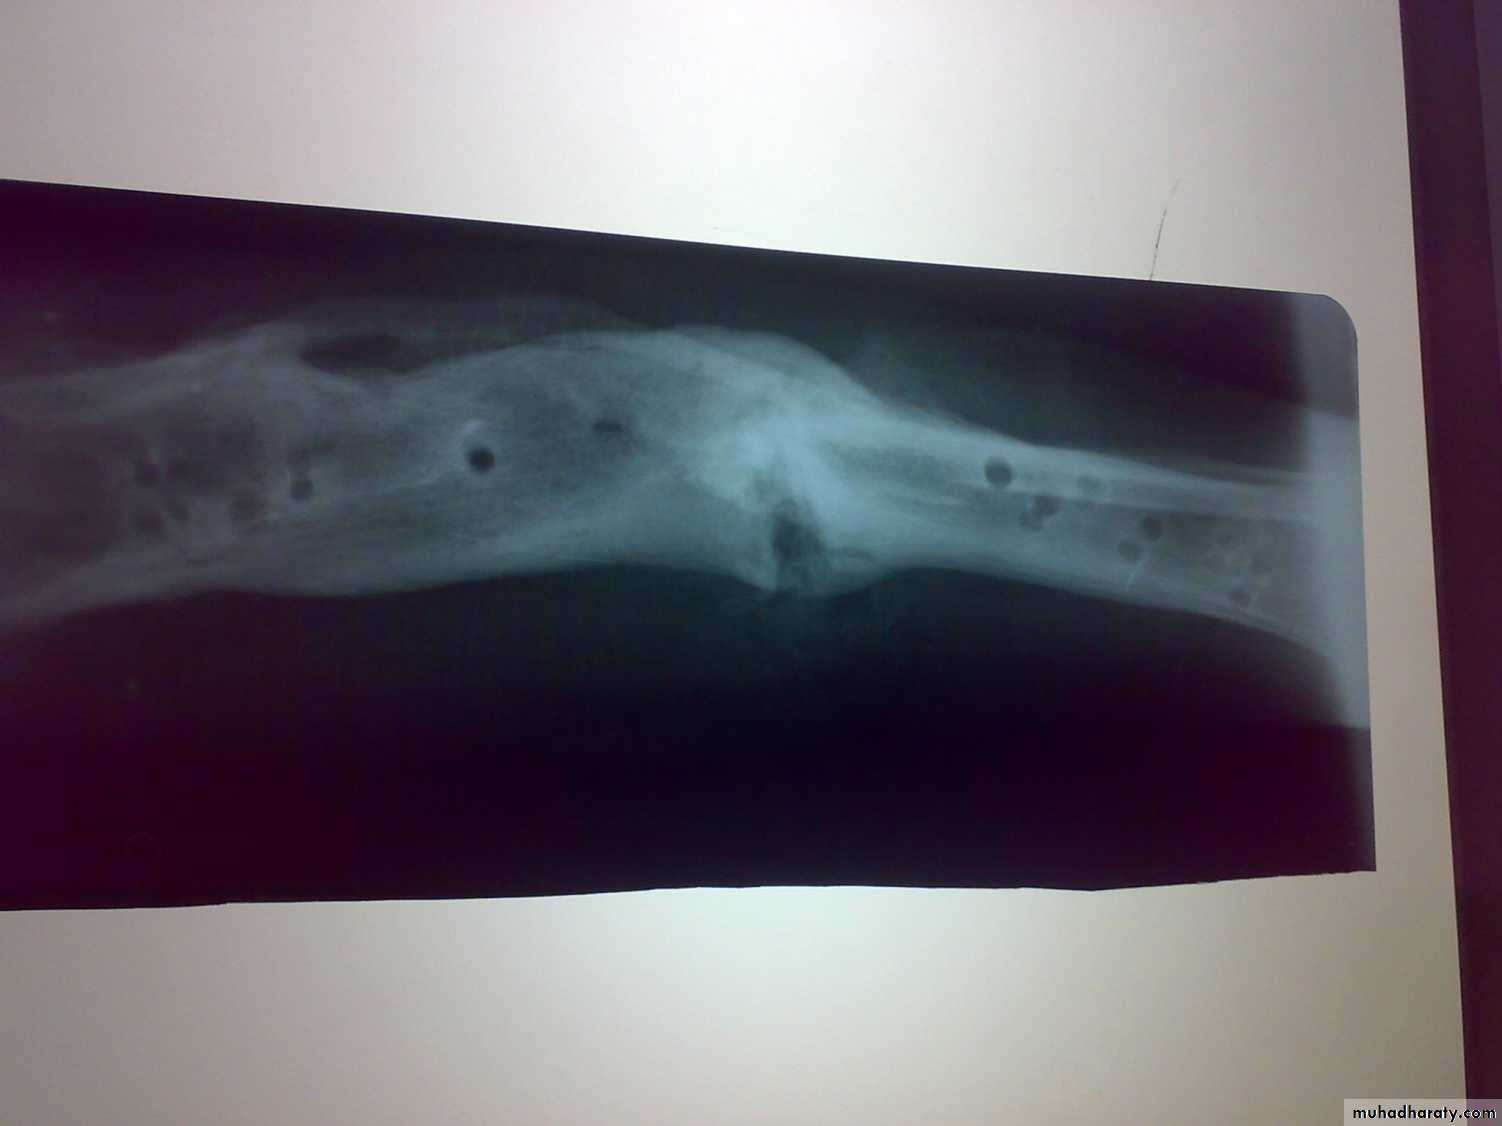

Chronic osteomyelitis

it may follows acute osteomyelitis, open fractures, and postoperative infectionsIt may caused by staph aureus, strept, proteus, pseudomonas, staph epidermidis or mixed infection.

There is segments of dead bones, sclerosis, cavities and chronic inflammatory infiltration.

Investigations include culture and sensitivity from infected tissues in depth of sinus , x-ray and other imaging studied.